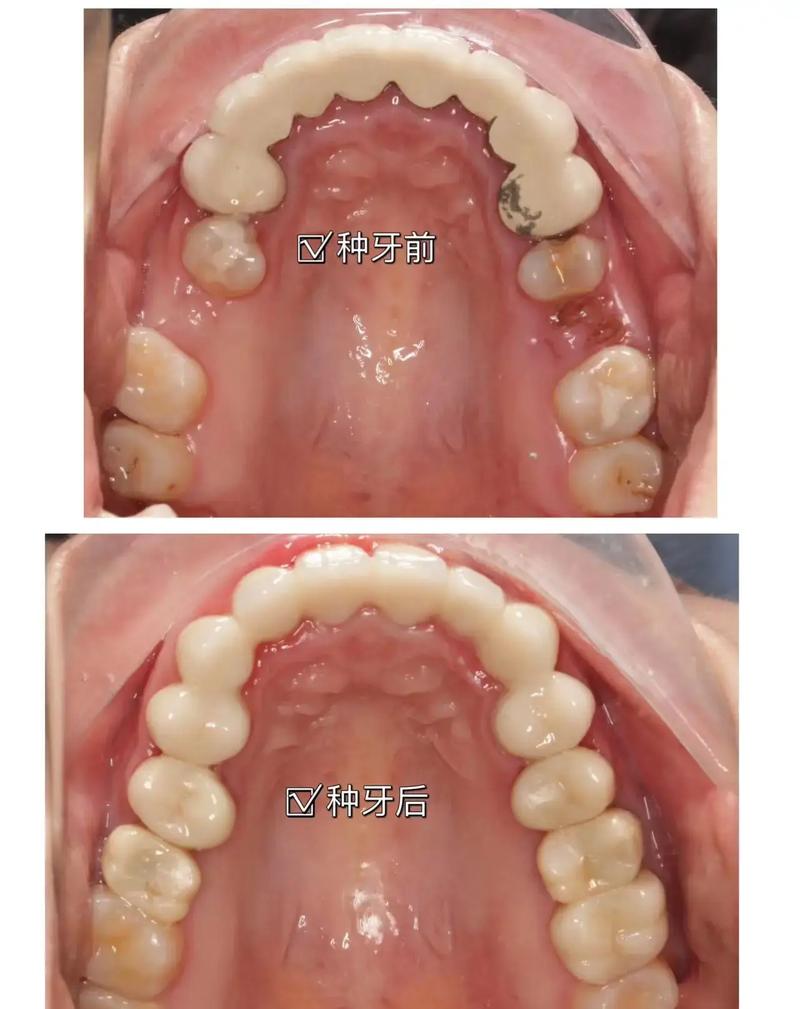

种植牙前后的牙龈沟变化是一个涉及生物学、解剖学和临床技术的复杂过程,其变化对种植体的长期成功至关重要,以下是种植牙前后牙龈沟变化的主要阶段和关键点:

种植牙前的牙龈沟状态

种植牙修复完成后的牙龈沟状态(长期目标)

理想状态(成功种植体的标志):

(图片来源网络,侵删)- 深度: 形成一个稳定、健康的牙龈沟深度,通常在 2-3毫米 之间(类似健康天然牙)。

- 形态: 形成圆钝、健康的牙龈袖口,紧密包裹在种植体基台周围,封闭龈沟底,这是防止细菌入侵种植体-骨界面的关键屏障。

- 健康: 探诊不出血或轻微出血(与天然牙标准一致),无溢脓,无附着丧失(种植体周围附着丧失是种植体周围炎的早期指标)。

- 颜色与质地: 龈缘颜色粉红、质地坚韧、有弹性。

- 美观: 与邻牙牙龈协调,高度、弧度自然。

种植牙前后的牙龈沟变化是一个从可能存在的病理状态(炎症、退缩、缺损),经历手术创伤和愈合重建,最终目标是达到一个稳定、健康、有良好封闭功能的袖口结构(深度2-3mm,探诊不出血,无附着丧失) 的过程。种植体周围健康的牙龈沟是防止种植体周围炎、确保种植体长期成功的天然屏障。